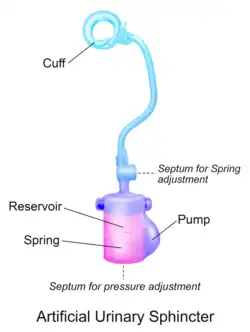

- O esfíncter urinário artificial com mola (2 componentes): manguito de controle e bomba.[3][4] O manguito de controle é colocado ao redor da uretra, e a bomba é inserida dentro do escroto. A pressão do circuito hidráulico é gerada pela mola na bomba. A pressão no espaço retropúbico não influencia esse tipo de esfíncter.

Outro modelo de AUS é o ZSI 375 (Zephyr Surgical Implants, Genebra, Suíça), apresentado em 2008.[11] É um aparelho inteiro com duas partes, um controle e uma bomba com mola integrada, que vem como uma única peça, pré-conectada e pré-preenchida.[1][12] Não há componente abdominal no ZSI 375 que junto com sua configuração pronta para implantar reduz o tempo de operação.[13] Além disso, evitando incisão abdominal previne cicatrizes pós-operatória na área retroperitoneal, assim, evitando a dissecação dos tecidos retroperitoneais, o ZSI 375 evita complicações cirúrgicas.[14][15]

Outra vantagem do ZSI 375 é a possibilidade de aumentar ou diminuir dentro do aparelho depois da implantação para encontrar a continência ideal para a satisfação do paciente. Estes ajustes ajudam a manter o controle de continência no caso de atrofia na uretra ou retenção urinária no pós-implantação. Os ajustes de pressão podem ser feitos através da adição ou remoção da solução salina através de uma seringa no escroto. Até 2019, mais de 4500 unidades do esfíncter urinário artificial do ZSI 375 foram implantados no mundo inteiro.[13][16][17]

Os dois modelos são preenchidos com solução salina dentro do sistema que é utilizado para gerar pressão e comprimir a uretra (para prevenir vazamentos da urina). O controle uretral é esvaziado manualmente através de uma bomba controlada manualmente, que fica no escroto, permitindo que o paciente esvazie a bexiga. O controle da uretra então reinfla automaticamente e o paciente torna-se continente novamente.[1][18]